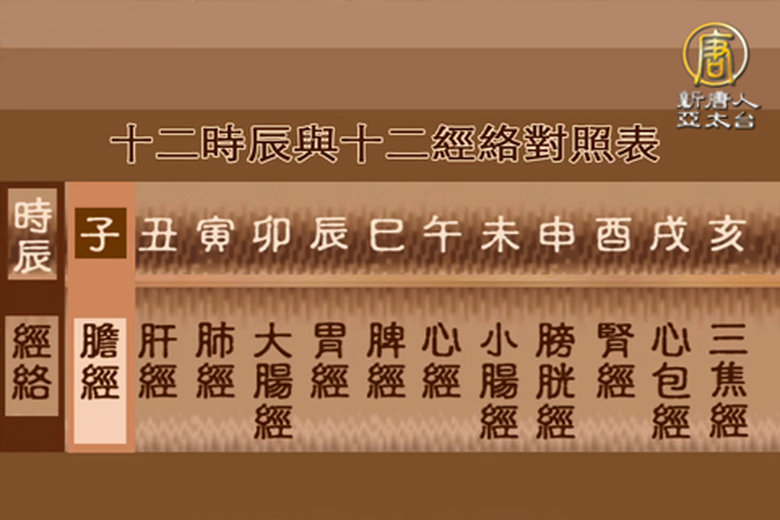

脾胃不適是現代人常見也習以為常的病痛,但現代人追求快速治療,時常去西藥房買止痛劑、止痛藥來緩解而已,使得病情日趨嚴重,而在中醫理論的觀點上,可不只是西醫那樣只看腸、胃,而是從心、情志上來診斷,看看鄭振鴻醫師怎麼說如何讓我們的「脾氣」提升~